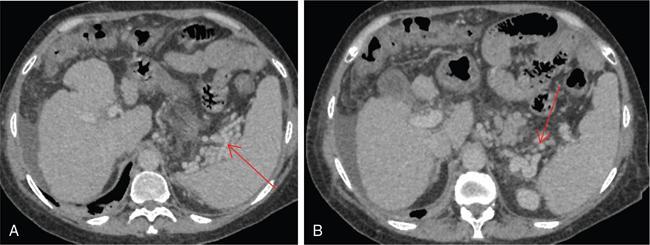

Shrinivas B. Desai, Ritu K. Kashikar, Aman Snehil, Ajay Jhaveri Cirrhosis is a late stage of irreversible scarring of the liver causing abnormality in liver structure and function. Multiple conditions and factors can cause repeated liver damage and scarring ultimately leading to cirrhosis. The most feared complication of liver cirrhosis is the development of hepatocellular carcinoma (HCC). Portal hypertension (PHT) is seen with a variety of conditions but cirrhosis happens to the most important cause. Imaging plays a vital role in noninvasive diagnosis and treatment planning of both cirrhosis and PHT. Liver imaging reporting and data system (LI-RADS) is a standardized reporting system assigning an observation risk of representing HCC. This chapter focuses on discussing aetiologies and imaging of PHT with a lucid review of L1-RADS 2018 version. The portal blood circulation is a unique circulatory circuit as it connects two capillary beds between the liver parenchyma at one end and the gastrointestinal tract and splenic parenchyma at the other end. The portal system ramifies in the liver and ultimately ends in the hepatic sinusoids from where the blood ultimately drains into the inferior vena cava (IVC). The portal vein (PV) originates from the capillary beds in the stomach, intestine and the spleen. The main PV is formed behind the neck of the pancreas by the confluence of the superior mesenteric vein (SMV) and splenic vein. It continues to the porta hepatis where it bifurcates into the left and right branches as it carries nutrient rich but oxygen poor blood to the liver (Fig. 9.9.1). The PV makes up for 75%–80% of the liver’s blood supply while the hepatic artery which arises from the celiac trunk makes up for the remaining 25%. A pathological increase in the portal venous pressure is referred to as PHT. PHT is most often a sequel of chronic parenchymal liver disease and leads to major life-threatening complications due to bleeding from the collateral circulation (most commonly oesophageal varices). Direct measurement of portal pressure (PP) is invasive and often not feasible in most patients and thus imaging plays an important role in the diagnosis of PHT and its complications. The normal portal venous pressure ranges between 5 and 10 mmHg, which is the equivalent of 7–14 cm H2O. The normal hepatic venous pressure gradient (HVPG) is the pressure gradient between the PV and the IVC, is typically 1–5 mmHg. Presence of PHT is indicated by a wedged hepatic venous pressure of more than 5 mmHg. Other definitions include a splenic pressure of more than 15 mmHg or an intraoperative PP of greater than 30 cm H2O. The complications of PHT are seen when HVPG is greater than 10 mmHg and hence this value defines clinically significant PHT. Variceal bleeding is seen with a pressure greater than 12 mmHg. In ideal conditions, the portal circuit is a high flow, low resistance circuit as it has to allow substantial flow rates of 700–1000 mL/min to the hepatic parenchyma from the gastrointestinal tract. Anatomical changes in the organization of the hepatic lobule can result in rise in the portal resistance. These can occur in the form of collagen deposition in the space of Disse, fibrotic scars formed due to regenerative nodule (RN) formation, loss of normal elasticity of the endothelium and distal venous thrombosis. Changes in splanchnic haemodynamics due to factors that increase splanchnic blood flow and increase in intrahepatic vascular resistance due to transformation of stellate cells into myofibroblasts also contribute to the increase in PP gradient. In Western countries, alcoholic cirrhosis and viral cirrhosis are the leading causes of PHT and oesophageal varices. The viral causes form majority of cases leading to cirrhosis and PHT in the Far East and Middle Eastern countries while Schistosomiasis remains an important cause in the African countries. Worldwide, nonalcoholic steatohepatitis (NASH) and hepatitis C are the emerging causes of chronic liver disease (CLD) and PHT. PHT can be classified as cirrhotic and noncirrhotic depending on whether it is associated with cirrhosis or not. This distinction is important as noncirrhotic causes like PV thrombosis are at high risk of development of bleeding but tend to have a better chance of surviving a variceal bleed than a patient with decompensated alcoholic cirrhosis due to preserved hepatic synthetic functions in the former. PHT can also be classified on the basis of the location of the pathology into prehepatic, hepatic and posthepatic causes. Hepatic causes can further be divided into presinusoidal, sinusoidal and postsinusoidal. The causes of portal hypertension have been denoted in Table 9.9.1. The direct measurement of the PP by measuring the HVPG is invasive, expensive not readily available in all patients. Thus, imaging plays an important role in the diagnosis of PHT. Various modalities are used for the imaging diagnosis of PHT. Ultrasonography (USG) and Doppler evaluation have the advantage of being inexpensive, readily available and bedside modality (Table 9.9.2). The role of ultrasound and Doppler in imaging of PHT is to: Grey scale imaging is useful in evaluating the splenoportal anatomy. The evaluation should begin with the liver morphology. Signs of cirrhosis like nodularity of the liver surface with relative atrophy of the right lobe and prominence of the left lobe and caudate should be looked for. Hepatic echotexture appears coarse and more echogenic (Table 9.9.3). Increase in portal venous diameter is a sign of PHT (Fig. 9.9.2). Portal venous diameter of more than 13 or 15 mm has low sensitivity for diagnosing PHT of only 40%–12.5%, respectively. Absolute measurement of the portal diameter as a sign of PHT is also fallacious as in presence of collateral circulation or hepatofugal flow; there may actually be a decrease in the PV diameter. Therefore, a more accurate sign is respiratory variation of PV diameter. An increase in PV diameter of less than 20% with deep inspiration has been reported to indicate PHT with a sensitivity of 80% and specificity of 100%. This has been reported to be an accurate indicator of cirrhosis. Hepatic vein straightness, uniformity of vein wall echogenicity and visualization of at least 1 cm segment of the hepatic vein are the parameters used for evaluation. Splenomegaly is defined as bipolar splenic diameter of greater than 12 cm or largest splenic cross-sectional area passing through the hilum of greater than 45 cm2, and occurs secondary to PHT (Fig. 9.9.3). A total of 65%–80% patients with cirrhosis have splenomegaly on ultrasound. Patients with cirrhosis due to viral hepatitis and primary biliary cirrhosis show splenomegaly more frequently than those with alcoholic cirrhosis. This is an accurate sign of PHT. USG is extremely sensitive with respect to detecting subclinical ascites. Perihepatic space is the most usual site of visualization of minimal ascites. In normal subjects, this ratio is approximately 0.07 and a value above 0.1 suggests the diagnosis of PHT with a 95% sensitivity and specificity. The normal spectral waveform of the hepatic artery is a low resistance flow pattern with forward flow in diastole and a resistivity index in the range of 0.5–0.7. In PHT, the resistivity index of the hepatic artery increases with high resistance flow pattern due to increased peripheral vascular resistance. Resistance index (RI) > 0.78 in the intrahepatic branches of the hepatic artery has been reported to have a sensitivity of 50% and a specificity of 100% for the detection of PHT (Fig. 9.9.11). Pulsatility index (PI) > 1.05 suggests severe PHT with a sensitivity of 86% and specificity of 88% (Fig. 9.9.11). Patency of hepatic veins should be evaluated to rule out Budd–Chiari syndrome as a cause of PHT. The normal hepatic venous waveform (HVW) reflects right atrial activity and this results in a triphasic waveform with one positive and two negative waves. In PHT, this waveform becomes monophasic or biphasic. A monophasic HVW has a sensitivity and specificity of 74% and 95%, respectively, in the diagnosis of severe PHT (Fig. 9.9.12). Dilatation of the splanchnic veins – the SMV and the splenic vein – more than 11 mm are suggestive of PHT with a sensitivity and specificity of 72% and 100%, respectively. A reduction in the respiratory variation of the splenic vein and SMV to less than 40% had a sensitivity and specificity of 79.7% and 100%, respectively, for the diagnosis of PHT (Fig. 9.9.13). The splenic artery reveals an increase in the resistivity index and an RI of >0.63 and a PI of >1 have a sensitivity and specificity of 84.6% and 70.4% for the diagnosis of PHT. Presence of portosystemic collaterals like patent paraumbilical vein, dilated left gastric and short gastric veins are 100% specific sign for PHT (Figs. 9.9.14–9.9.16). Recanalization of the paraumbilical vein, known as the Cruveilhier–Baumgarten syndrome is observed in 43% of patients with PHT, and this is the easiest collateral to assess during the US examination. Various portosystemic collaterals that occur in PHT have been discussed in details in subsection on CT findings in PHT. No Doppler parameter is considered reliable enough to measure PP with sufficient accuracy for use in clinical practice. Oesophageal varices are often present in patients with portosystemic collaterals. Appearance or increase in number of collaterals along with splenomegaly has a high association with variceal formation and growth. USG helps in diagnosis of prehepatic causes like portal stenosis or thrombosis by demonstrating the patency and morphology of the splenoportal system. Arteriovenous fistulae and tumours causing vascular thrombosis as aetiology can be readily detected. USG helps in diagnosis of features of cirrhosis and thus helps differentiate noncirrhotic causes of PHT. USG allows diagnosis of fatty liver disease, which is an emerging cause of cirrhosis. Among the posthepatic causes, USG aids in establishing the diagnosis of Budd–Chiari syndrome by demonstrating the patency and morphology of the IVC and hepatic veins. Owing to the inability of CT to detect flow direction, portal flow rates or pressure gradients, CT is not the primary modality in diagnosis of PHT. Similar to USG dilatation of portosystemic system is a feature of PHT (Fig. 9.9.17). Changes in cirrhosis if present can be seen in the form of surface nodularity, nodules and fibrous septae. CT plays an important role in diagnosis of portal venous thrombosis and evaluating its extent. An acute thrombus is seen as a hypodense filling defect in the vessel causing distension of the venous lumen. Surrounding fat stranding can be seen. A chronic thrombus appears as an eccentric filling defect usually along the wall and is often associated with decrease in vessel diameter. Calcification may be seen in chronic thrombi. Multidetector computed tomography (MDCT) is a useful tool to evaluate portosystemic collateral circulation and recognize complications of PHT. 3D angiography can help understand portal venous and complex variceal anatomy and plan treatment. The various portosystemic collaterals are discussed below. They can be classified into those draining into superior vena cava (SVC) and those draining into the IVC. Magnetic resonance imaging (MRI) is a noninvasive modality used in the evaluation of PHT without the use of ionising radiation. It provides evaluation of parenchymal abnormalities, collaterals and characterization of tumours (Fig. 9.9.28). Spin echo sequences allow characterization of liver masses and liver parenchyma. Loss of flow void allows for detection of thrombosis. Time-of-flight (TOF) angiography is useful in assessing the portal venous system and allows for successful detection of PV thrombosis. The disadvantages of TOF are motion artefacts caused by breathing, long acquisition times and incomplete coverage of the portal venous system. Novel imaging techniques include phase contrast, T1 mapping and magnetic resonance elastography (MRE). The advantage of phase contrast over TOF imaging is that phase contrast imaging acquires information regarding the flow direction in addition to the information regarding the flow velocity. On-phase contrast images signal within vessel is hyperintense when flow is cranial and hypointense when flow is caudal. Look-Locker imaging technique using gradient echo (GRE) MRI sequences with inversion recovery pulse is used to quantify fibrosis by measuring precontrast T1 relaxation times. Interventions in PHT can be aimed at diagnosis or more commonly at management of complications of PHT. HVPG measurement, which is the gold standard for the diagnosis of PHT, can be achieved through cannulation of the PV. Transjugular hepatic biopsy is another diagnostic invasive technique that also allows indirect measurement of PP. Disadvantages include deterioration of hepatic function caused by diversion of portal venous blood flow and shunt dysfunction. TIPSS is contraindicated in patients with congestive heart failure, severe pulmonary hypertension, severe tricuspid regurgitation and hepatic failure. In this technique, a catheter is advanced from the femoral vein into the outlet of the gastrorenal, usually in the region of the left renal vein. The shunt is then occluded with a balloon and sclerosant is injected retrograde to occlude the gastric varices. Histological development of RNs surrounded by fibrous septae in response to chronic liver injury, progressing PHT and end-stage liver disease is termed as cirrhosis. Although initially considered an end-stage phenomenon in CLD, recent evidence suggests that the histological fibrosis can be reversible in early stages with the initiation of specific therapies, for example, in viral cirrhosis with the initiation of antiviral therapy. The one-year mortality rate in cirrhosis varies widely from 1% to 57% depending on the occurrence of complications. Cirrhosis can have a wide variety of causes ranging from congenital to acquired and infectious to noninfectious. It is also a major aetiologic risk factor for the development of HCC. Imaging plays an important role in aetiologic diagnosis of this diverse entity as well as in the diagnosis and management of its complication and surveillance for oncological transformation.